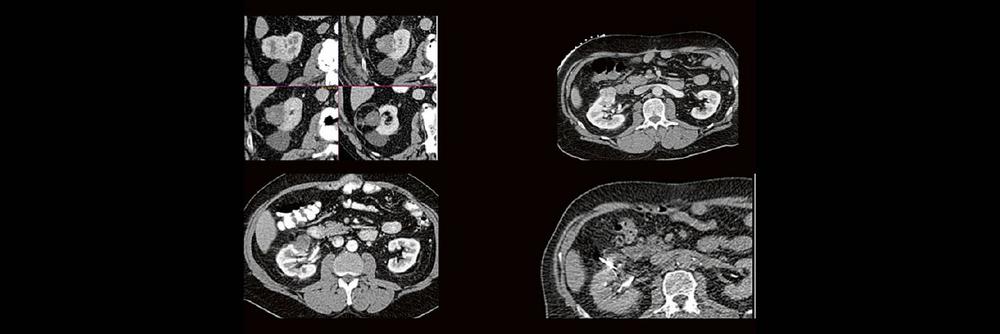

Back to the roots! Gute Kenntnisse der Anatomie sind der Schlüssel zur guten Planung, Durchführung und richtigen Diagnosestellung im CT des Abdomens. Lernen sie unverkrampft

- richtiges Kontrastmittel-Timing im Bild erkennen

- Anatomie in Pathologie übersetzen

Haben Sie es erkannt? Probieren Sie selbst im lockeren Fallquiz zum mitraten.